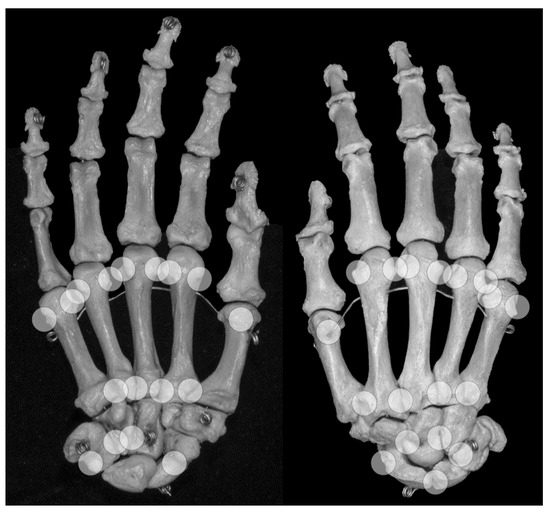

Figure 4. Locations of anatomical pseudoerosions. Overview on possible locations of anatomical pseudoerosions as summarized in Table 3. Right skeletal hand, on the left view from palmar, on the right view from dorsal.

4.1. Anatomic Pseudoerosions

An anatomic pseudoerosion can be defined as a normal concavity of a bone outlined by a smooth and thin calcified zone with the potential for a false-positive misinterpretation of an erosion. In this form, the term pseudoerosion is more precise than “notch” or “bony depression” and may be preferred as it contains a prognostic impact for the imaging assessment of arthritis. Such clinically oriented annotations, examples are the scaphoid waist and the metacarpal neck as typical sites for fractures, have been in use in traumatology and may be of help in the assessment of arthritis-related erosions, too (list of described pseudoerosions in Table 3, an overview of anatomical pseudoerosions in the hand may also be found in Figure 4).

Grooves due to ligament or tendon insertions have a varying appearance as described in the enthesis concept by Benjamin and McGonagle [79]. Such prominent grooves can cause the appearance of a pseudoerosion (Figure 2a). A groove may occur in three forms: (1) at a non-apophyseal direct tendon or ligament attachment where the uncalcified components of the enthesis enters the bone, (2) at an apophysis with overhanging edges, or (3) at an incomplete apophysis, a jutty, at the indirect attachments of a tendon or ligament with a tangential transition into the periosteum. For example, pseudoerosions resulting from the first form are the metacarpal ligament insertions at the bases of the metacarpal bones [80]. At the dorsal aspect of the triquetral bone, such a pseudoerosion may be formed by the distal insertion of the radiotriquetral ligament along with other components of the dorsal radiocarpal ligament. On the capitate, on which several strong carpal ligaments have their insertion, and many other carpal bones, intercarpal ligaments may cause pseudoerosions [51]. Examples for the second form may be the non-spherical form of metacarpal and metatarsal heads, which can be explained by the collateral ligament complexes running laterally and medially with smoothly outlined shallow metacarpal grooves containing these structures. At the metacarpals, these grooves are bordered by little tubercles for the proximal attachment of the collateral ligaments (Figure 4) [81]. Moraes do Carmo et al. [54] identified three concavities in the first metacarpal head (intersesamoid, ulnar, and radial) and two in those of the fingers (ulnar and radial). They described dorsal depressions of the metacarpal heads due to the extensor digitorum tendons in one third of their anatomic specimens which correlated with observations with ultrasound made by Boutry et al. [82,83]. A similar study was done for defining pseudoerosions of the metatarsal heads by Torshizy et al. [55] who described anatomic variations in the normal osseous concavities of the lateral and medial aspects of each metatarsal head. Typical jutties, i.e., examples for the third form of grooves, are the small round or oval subcapsular notches at the proximal phalangeal bases [80,84]. At the Achilles tendon insertion, proximal to its jutty shallow irregularities beneath the calcaneal bursa may represent true erosions [85].

Osseous sulci are commonly roofed with a ligament, fascia or other fibrous tissue, thus forming an osteofibrous channel for a tendon within a synovial tendon sheath. A subcapital neck of the distal metacarpal and the metatarsal bones is a small metaphyseal narrowing that may cause a pseudoerosion on projection radiographs, ultrasound or MRI [86]. At the distal fifth metacarpal bone, due to its slight varus angulation this neck may be more prominent.